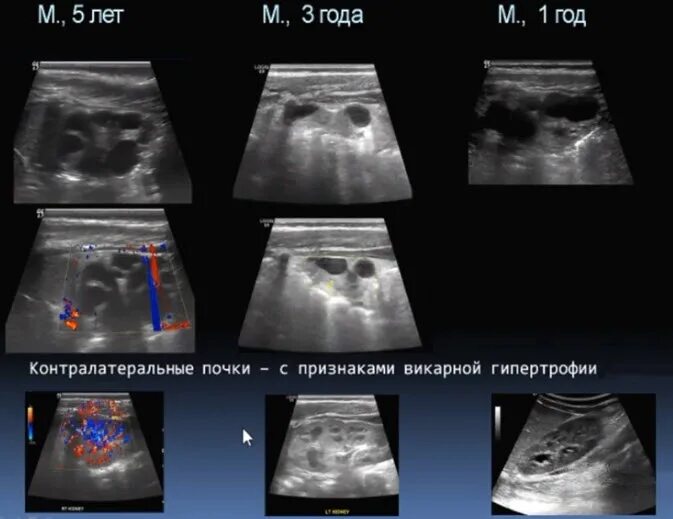

Мультикистозная почек плода